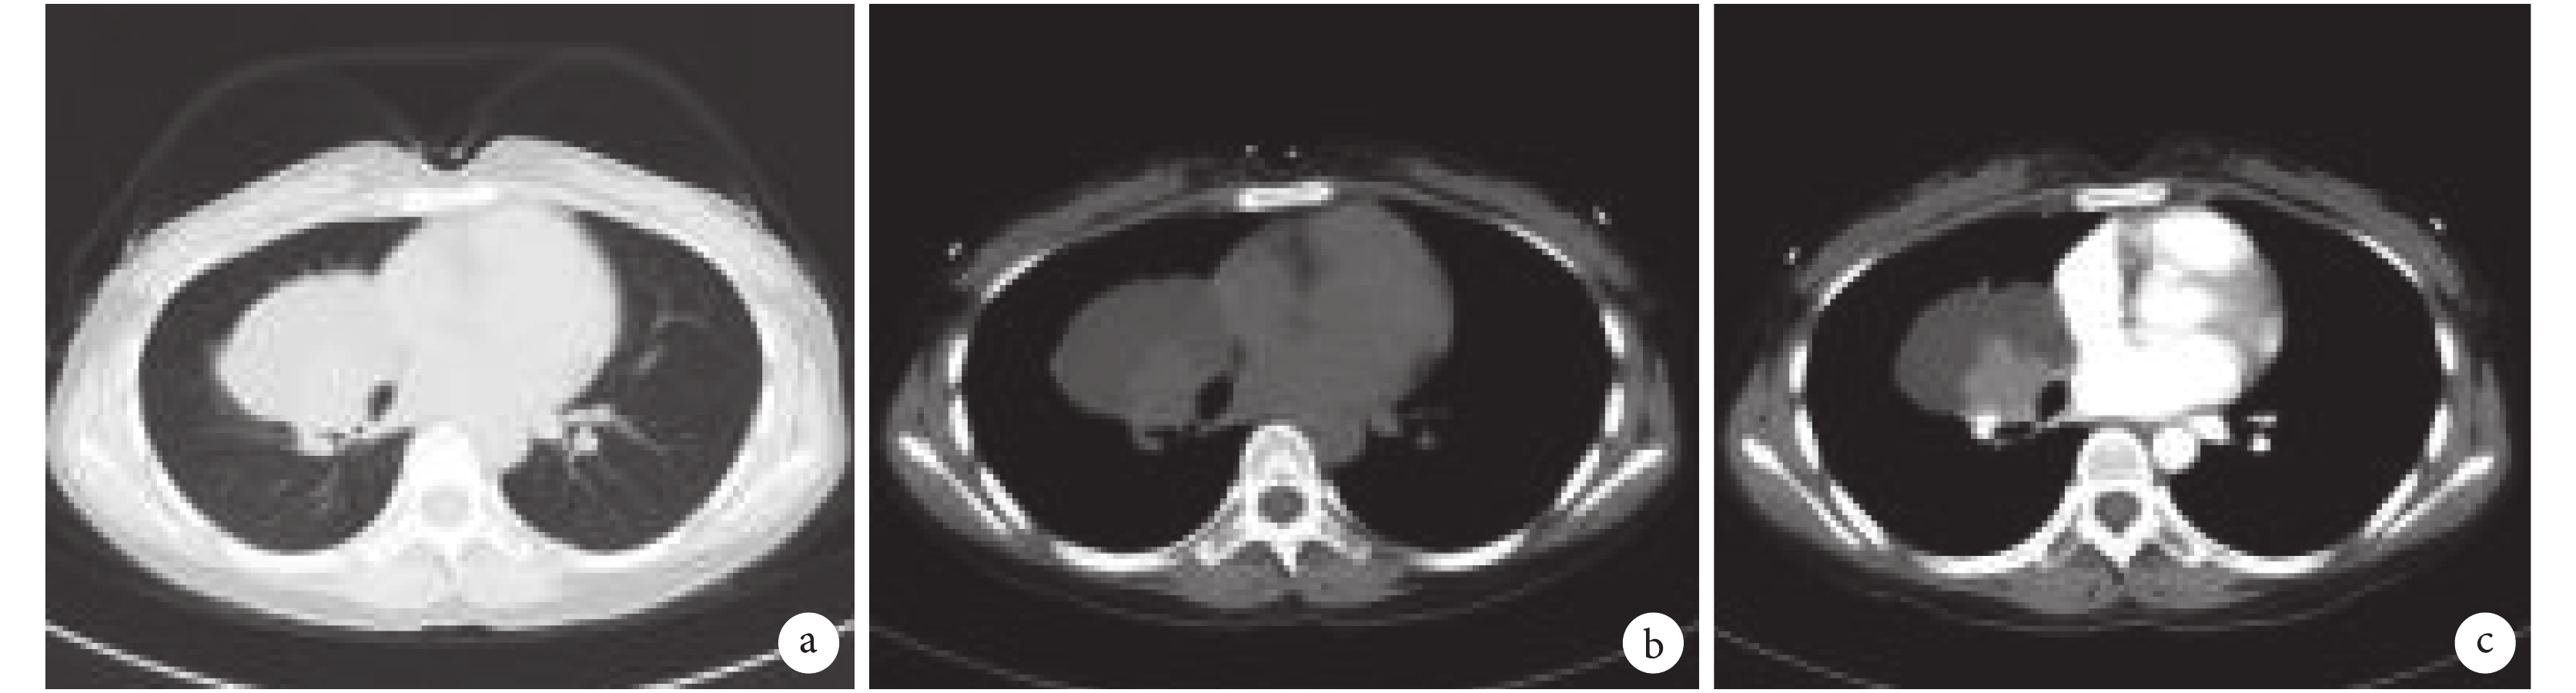

a. 肺窗;b. 縱隔窗;c. 增強 CT。右肺中葉占位性病變,右肺中葉支氣管閉塞,平掃示腫塊邊緣光滑,增強掃描成囊實性改變,內可見分隔,實性成分呈中度均勻強化,與鄰近支氣管分界不清,未見明顯淋巴結腫大、鈣化影、壞死灶

既往史無特殊,無不良嗜好。入院體格檢查:T 36.7 ℃、P 85 次/min、R 18 次/min、BP 101/69 mm Hg(1 mm Hg=0.133 kPa)。急性面容,神清,皮膚未見皮疹,未觸及淺表淋巴結,鞏膜無黃染,口唇無發紺,扁桃體不大,頸軟,氣管居中,無頸靜脈怒張,甲狀腺不大,胸廓對稱無畸形,雙肺可聞及散在濕性啰音,以右肺中下葉明顯,無哮鳴音及胸膜摩擦音;余未見異常。完善胸部 CT 平掃+增強檢查,顯示右肺中葉支氣管閉塞,周圍形成 31 mm×35 mm 不規則軟組織腫塊,增強掃描中度強化,腫物外周見較大不規則囊性低密度區,右下葉肺見多發斑片狀高密度影,邊界不清;提示右肺中葉占位性病變并右中葉肺黏液潴留,右下葉肺炎(圖 1)。纖支鏡檢查:可見右支氣管管腔見較多白色分泌物,中葉開口見新生物表面覆蓋少量壞死物質,觸及易出血,周圍支氣管黏膜充血及水腫,管腔完全閉塞,提示右中葉病變,腫瘤不能除外,建議再次支氣管鏡檢查;病理診斷:(右中葉)非角化型鱗癌?免疫組織化學檢查示 CK(+)、P40(+)、P63(+)、CK5/6(++)、Vimentin(–)、CD56(–)、CgA(–)、CK7(弱+)、Napsin-A(–)、Syn(–)、TTF1(–)、Ki-67(5%+);灌洗液細胞病理+DNA 倍體分析見較多纖毛柱狀上皮細胞,少量淋巴細胞,部分上皮細胞增生明顯,未見 DNA 異倍體;右中葉刷檢物見少量絲狀真菌生長,未找到脫落細胞,灌洗液結核分支桿菌核酸檢測陰性。淺表淋巴結彩色超聲探及雙側頸部及腋窩淋巴結:雙側頸部探及多枚實性低回聲結節,部分皮髓質結構欠清,左側 16 mm×8 mm,右側 11 mm×5 mm;雙側腋窩探及多枚實性低回聲結節,左側 11 mm×5 mm,右側 12 mm×5 mm。